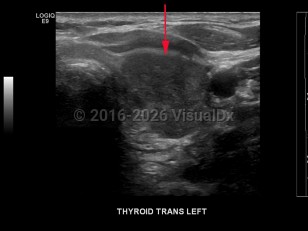

Thyroid cancer is classified based on histologic features:

- Papillary thyroid cancer – The most common type of thyroid cancer (approximately 85% of cases), often with diagnosis at an early stage with good overall prognosis. Characteristic histologic findings include psammoma bodies, cleaved nuclei with an "Orphan Annie" appearance, and the formation of papillary structures. Of note, it is now suggested that the encapsulated follicular variant of papillary thyroid carcinoma, which has a very low risk of adverse outcome, be reclassified as noninvasive follicular thyroid neoplasm with papillary-like nuclear features.

- Follicular thyroid cancer – The most common type of thyroid cancer in iodine-deficient regions of the world. It is often difficult to diagnose with fine-needle aspiration due to a lack of distinguishing features. Prognosis is poor if diagnosis is made at an advanced stage of disease.

- Anaplastic thyroid cancer – A poorly differentiated and aggressive form of thyroid cancer. Most patients die within 6 months of diagnosis.

- Medullary thyroid cancer – This can either be sporadic or familial as part of multiple endocrine neoplasia type 2A (MEN2A), type 2B (MEN2B), or medullary thyroid cancer without other features of MEN. Surgical resection is the preferred method of treatment, with elevated calcitonin levels post-surgery indicating residual disease.